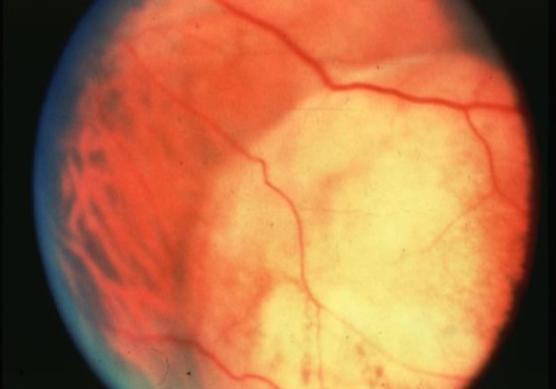

choroidal melanoma

melanoma

melanoma

melanoma

melanoma

melanoma

melanoma

melanoma

melanoma

melanoma

melanoma

melanoma

melanoma

melanoma

melanoma

melanoma

melanoma